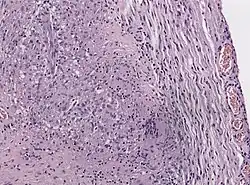

The cause of Tolosa–Hunt syndrome is not known. The disorder is thought to be, and often assumed to be, associated with inflammation of the areas behind the eyes (cavernous sinus and superior orbital fissure).[8] These granulomatous inflammations involve lymphocytes, plasma cells, and multinucleate giant cells. Clinical cases have shown that the disorder consists of the inflammation of multiple cranial nerves, with the highest prevalence of ocular motor nerves. In some cases, it also involves the inflammation of sensory nerves, specifically the trigeminal nerves.

Due to the nature of the disorder, biopsy has been recommended as the best tool to assess whether a patient has the disorder or not.